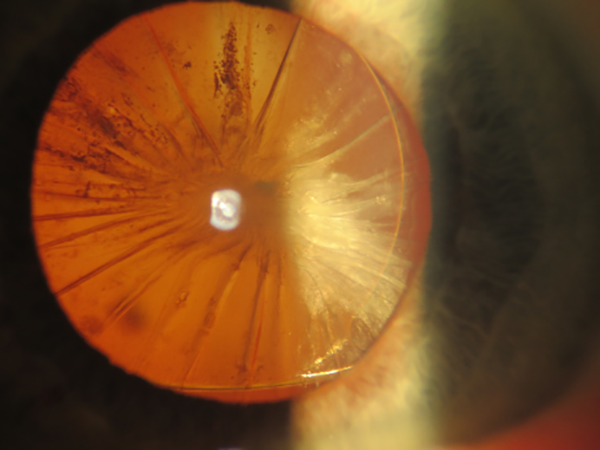

Fimosis capsular anterior completa en paciente pseudofáquico con lente de cámara posterior.